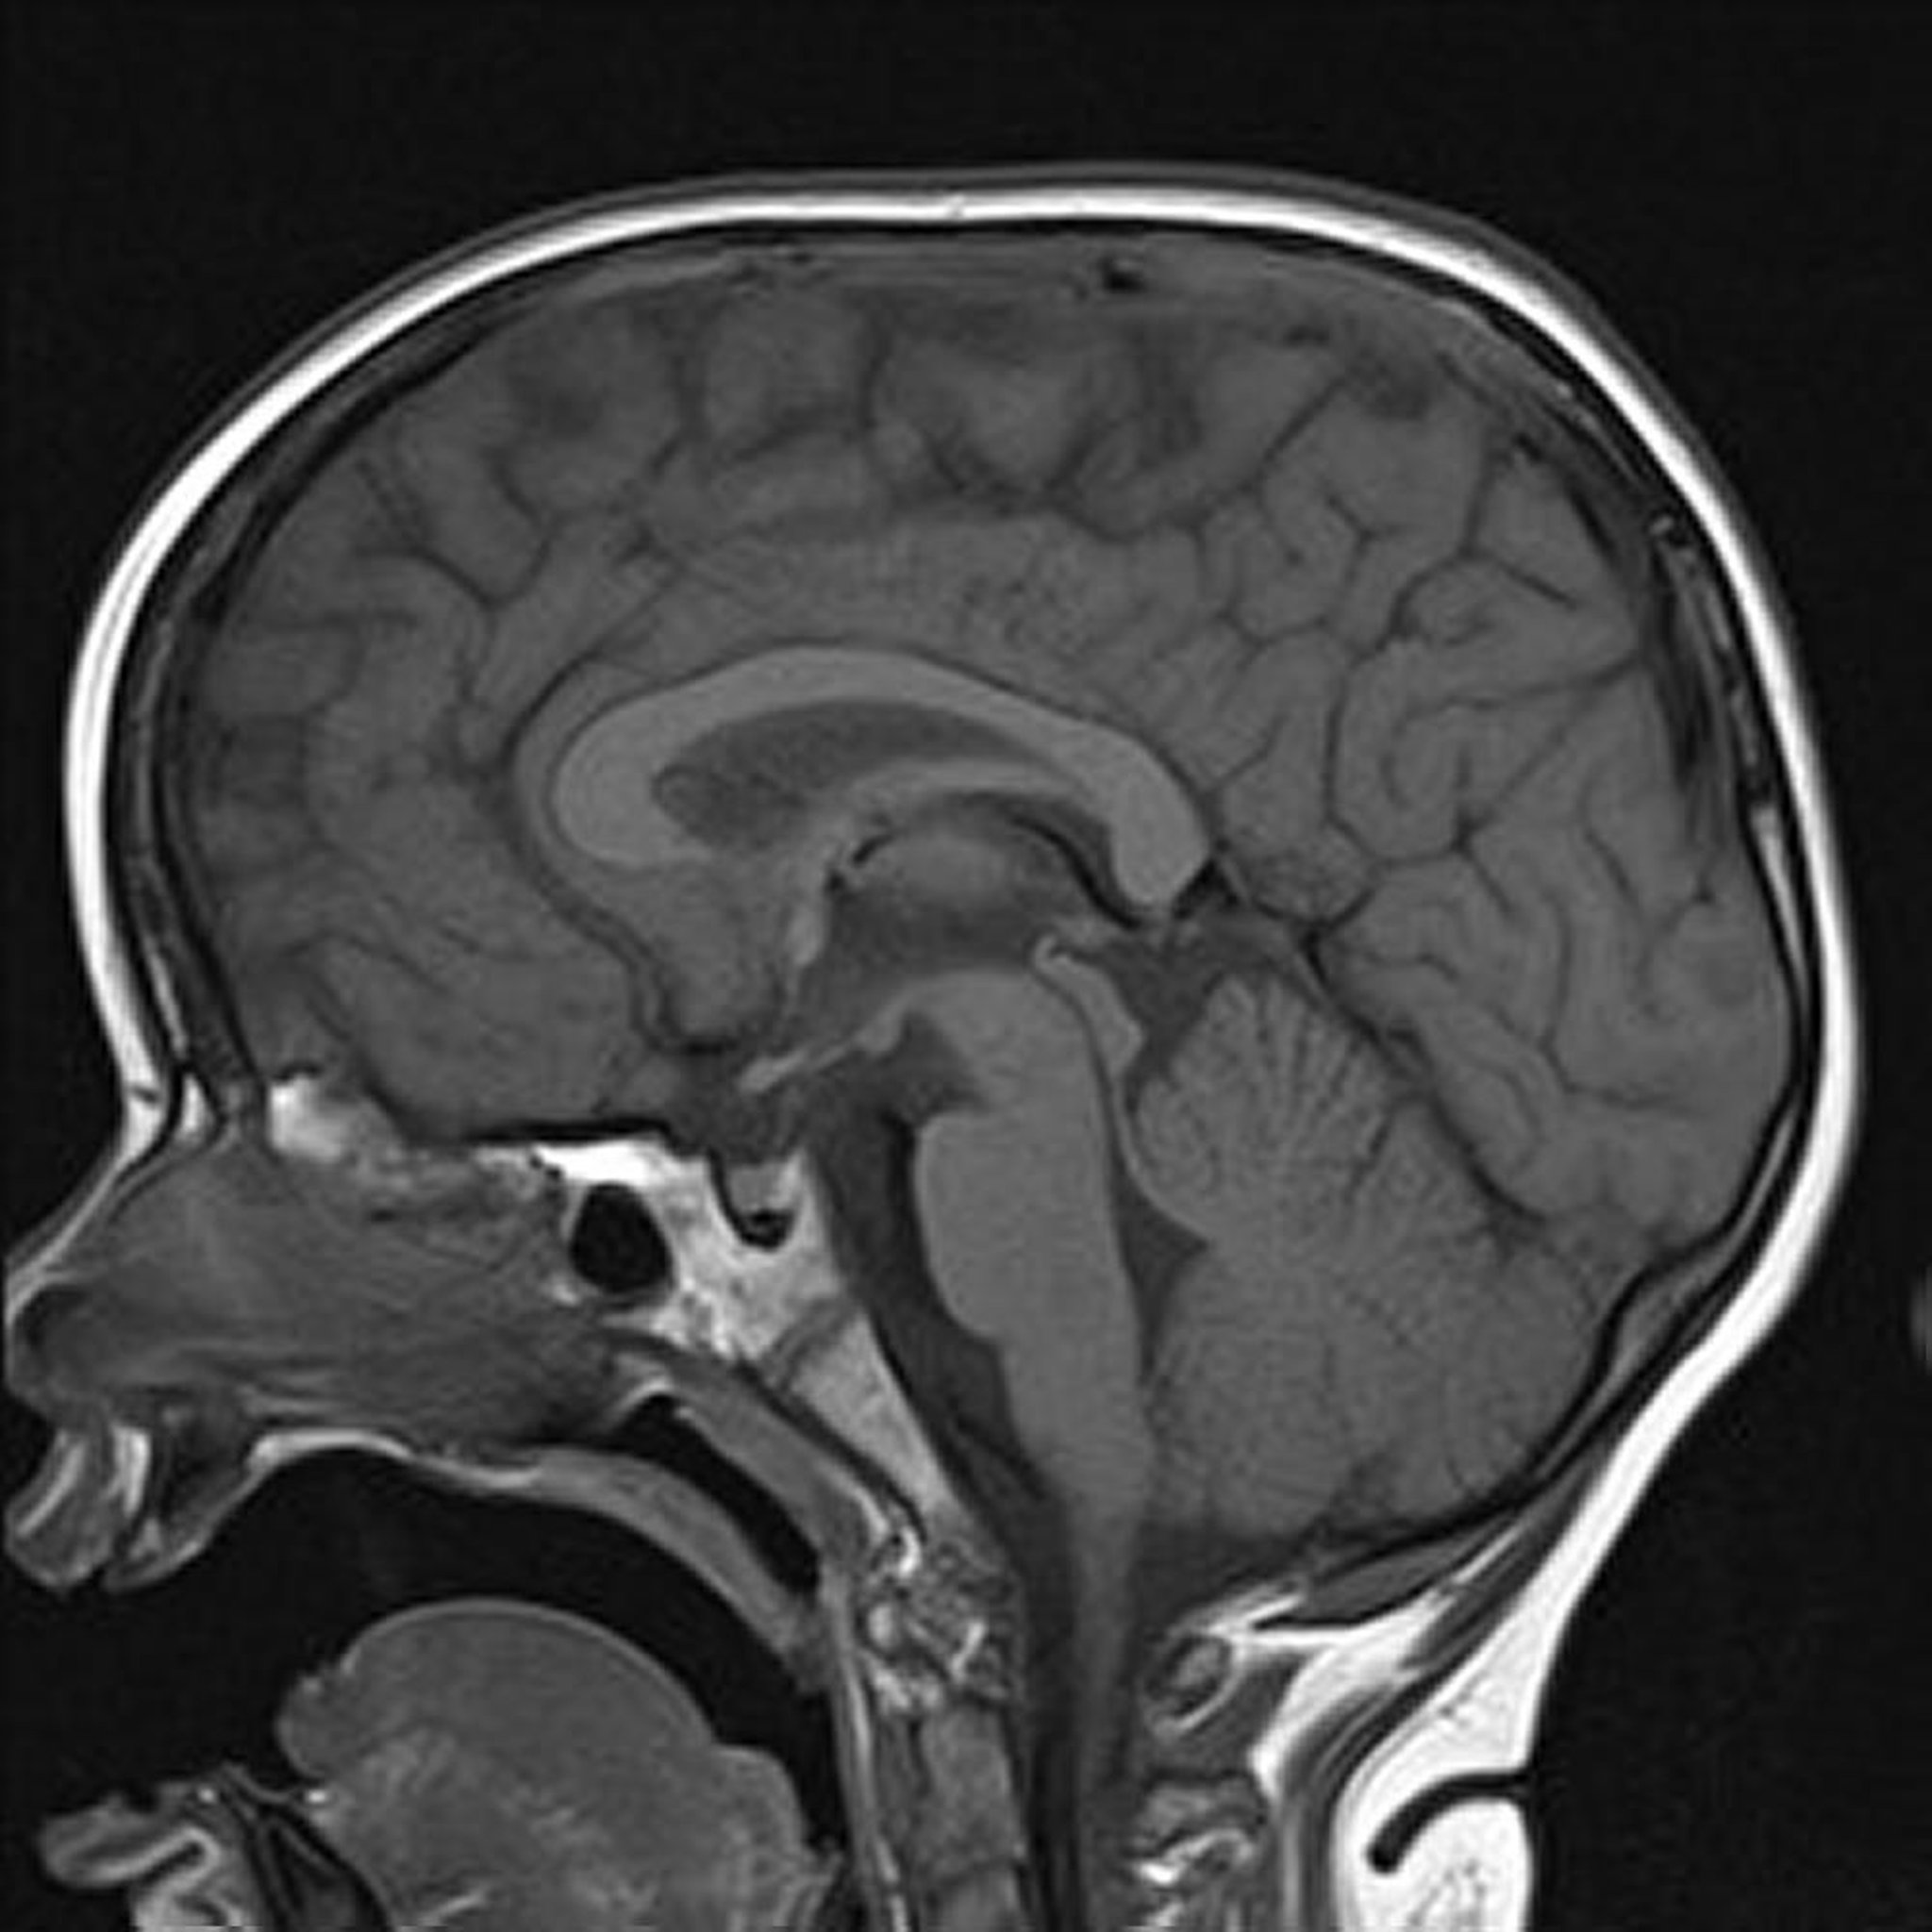

IRM pondérées en T1

L'image sagittale pondérée en T1 du cerveau montre des structures médianes normales.

Image courtoisie de Hakan Ilaslan, MD.